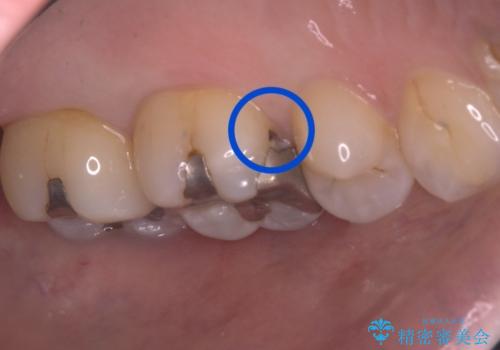

- 主訴:詰め物と歯の境目によごれがいつも溜まっている。フロスを通すと引っかかる。

保険適用のメタルインレーと歯質の境目が、歯質が欠けてしまったのか大きなくぼみ汚れが停滞しやすい状態になっていました。歯冠色材料でのやり替えを希望されたため、セラミックインレーでのやり替えとなりました。

左上6番に入っている保険適応のメタルインレーと歯質との境目(近心側室エリア)に不適部位を認め、そのくぼみに汚れが停滞しやすい状態となっていました。

適合性・審美性を考慮し、セラミックインレーでのやり替えとなりました。